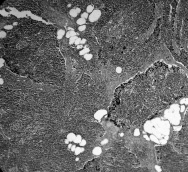

Рис. 3. Многофокусный рост папиллярного рака щитовидной железы. Окраска гематоксилином и эозином. X 100.

II.Многофокусный рост опухоли (мультицентричность). В отличие от фолликулярных карцином, многофокусный рост папиллярного рака встречался достаточно часто (рис. 3), особенно при неинкапсулированном раке смешанного (фолликулярном варианте папиллярного рака) строения. В случаях многофокусного роста папиллярных карцином чаще наблюдалось регионарное метастазирование.